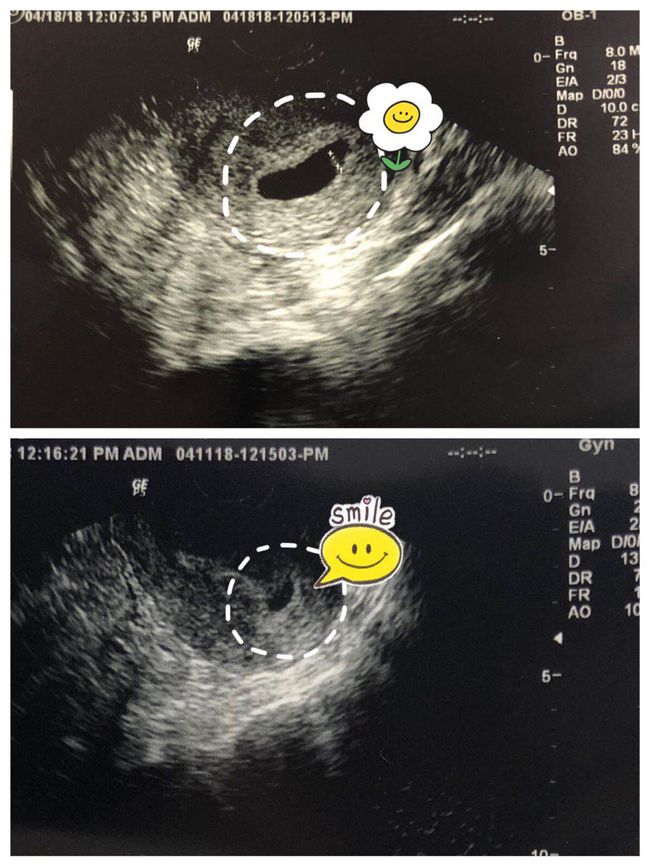

通过定期产检,医生可以了解胎儿的发育情况,从而对预产期进行更准确的判断。